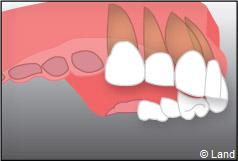

– le remplacement d’une dent unitaire. Grâce à ce procédé, il n’y a pas de mutilation des dents voisines.

– le remplacement de plusieurs dents manquantes par un bridge sur implants. Cela évite l’appareil amovible.

Exemple d’un implant unitaire pour remplacer une dent antérieure manquante.